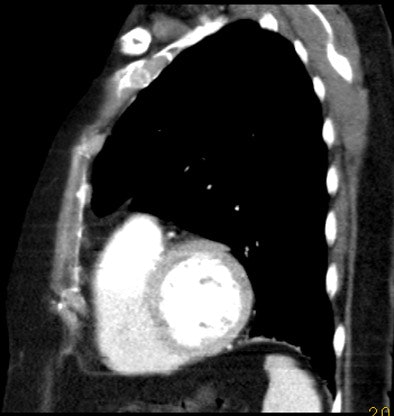

| An 81-year-old woman with acute chest pain and suspicion of acute pulmonary embolism. Short-axis images obtained at end-diastolic (above) and end-systolic (below) phase of the cardiac cycle using ECG-gated 16-slice CT. Right and left ejection fractions were measured at 43% and 41%, respectively. Note the variation of both ventricle volumes and myocardium thickness throughout cardiac cycle. On the same examination, slab MIP oblique reformatted images (bottom) revealed hypodensity in the right pulmonary artery and arteries of the right lower lobe consistent with acute pulmonary embolism. All images courtesy of Dr. Emmanuel Coche. |